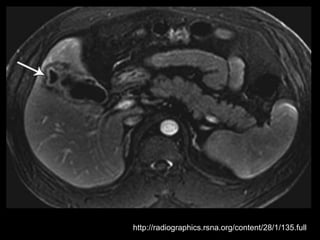

Colecistite Xantogranulomatosa

Na TC:

Os cálculos biliares e o espessamento irregular

semelhante a uma massa da parede da VB são as

anormalidades mais comuns.

Vários estudos relataram que os nódulos

hipoatenuantes intramurais vistos na TC

representam uma lesão xantogranulomatosa, um

abscesso ou a combinação de ambos;

Realce da superfície luminal(70%) correspondia à

presença de uma camada epitelial.

O radiologista deve distinguir entre a colecistite

xantogranulomatosa e o carcinoma da vesícula

biliar

Linha de mucosa evidente

Realce da superfície luminal

Nódulos intramurais hipoatenuantes(TC) ou com

sinal alto(RM T2)